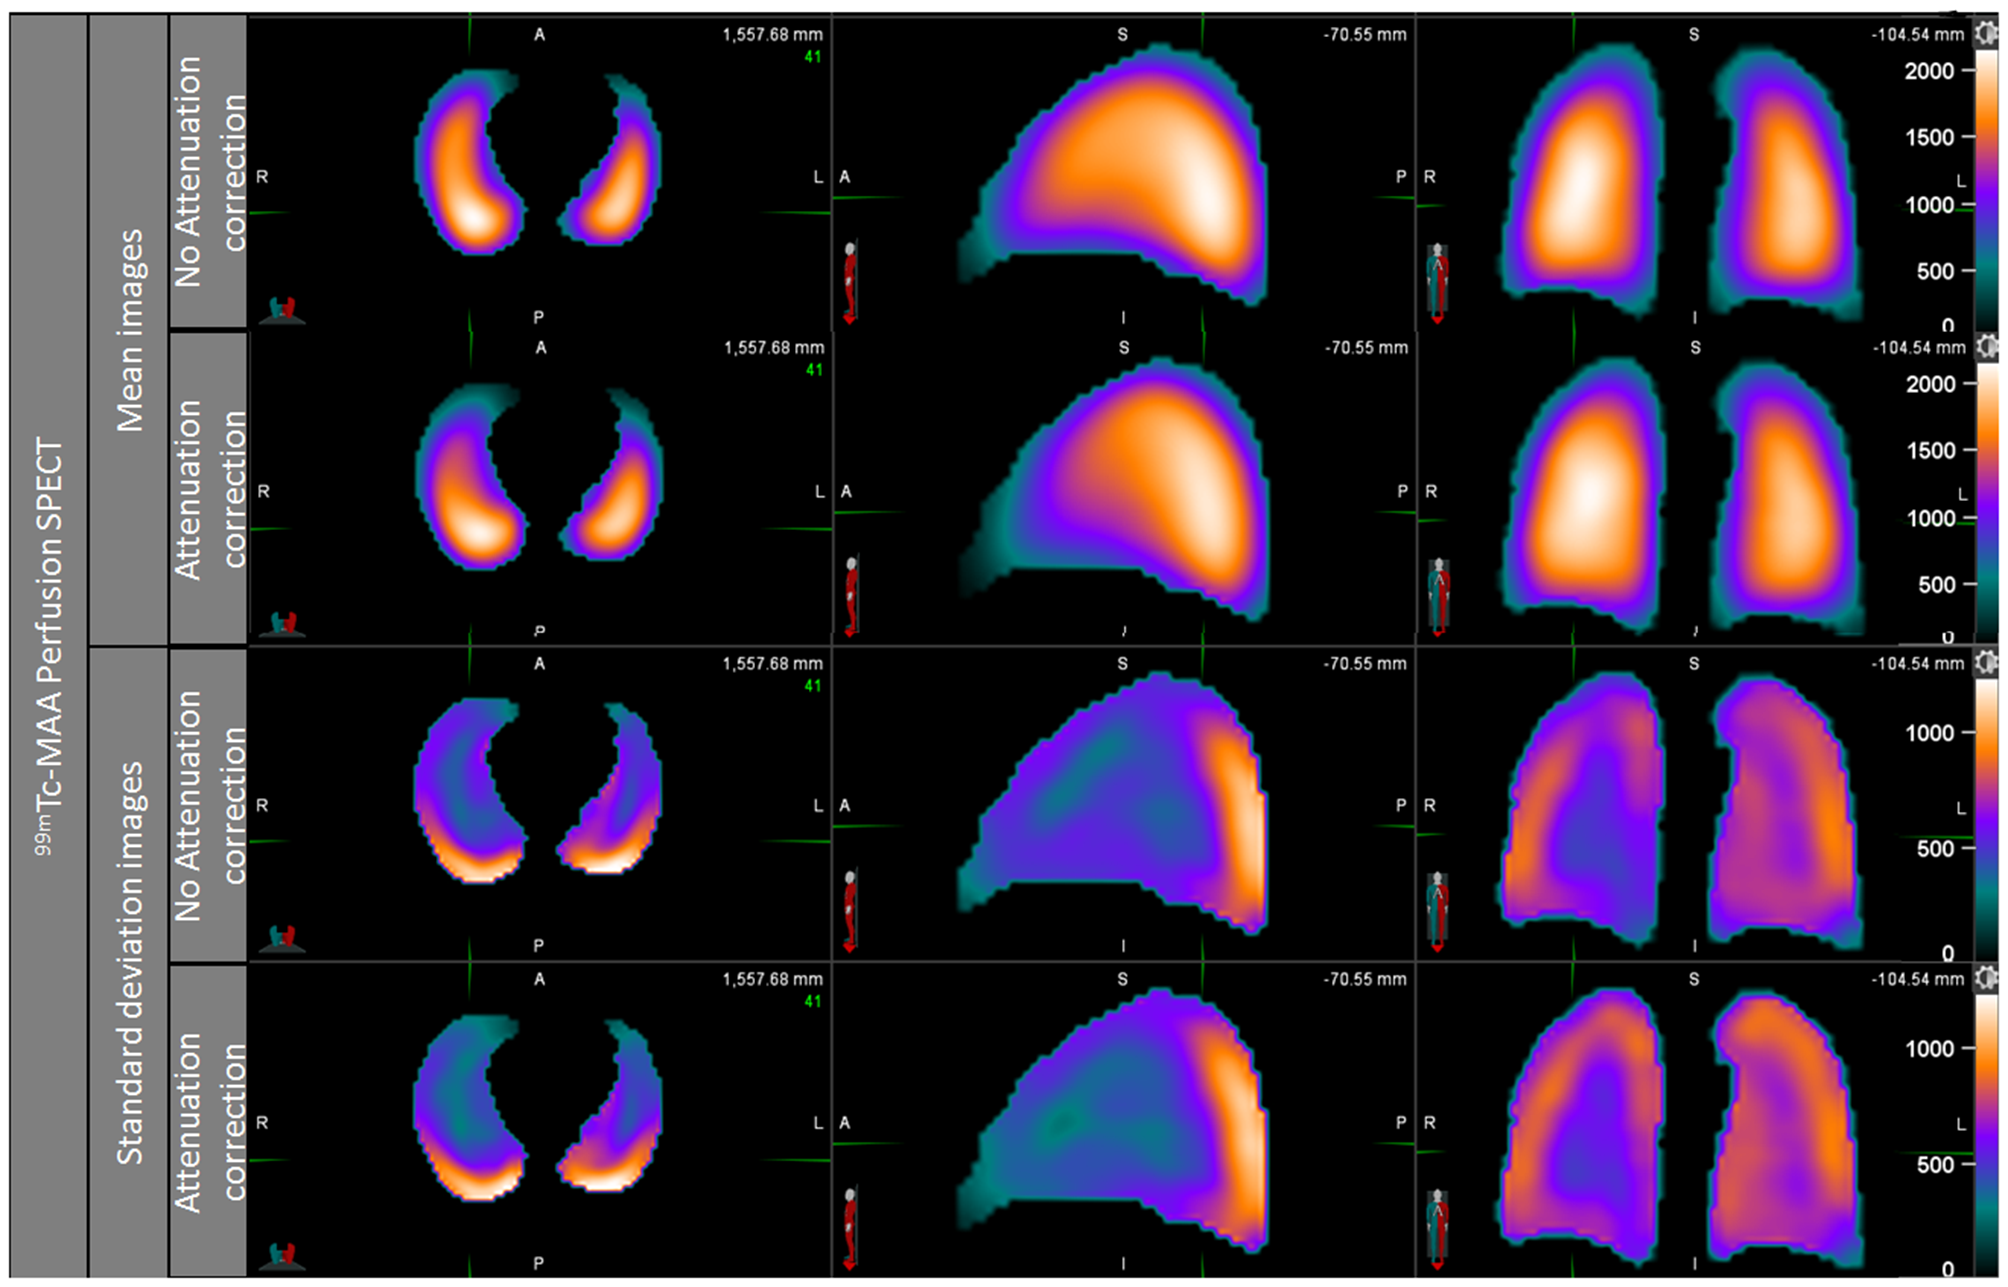

NoAC and AC perfusion statistical maps are shown in Figure 2. Images showed a continuous negative posterior to anterior gradient, majored on the AC mean map. The perfusion standard deviation (SD) maps showed higher variability in the periphery of the lungs, but especially in the posterior areas of the lungs. This high variability in posterior area was equivalent on AC and NoAC images.

Figure 2

Perfusion mean map and standard deviation map, noAC, and AC.

The ventilation mean map showed a slightly positive posterior to anterior gradient on NoAC mean ventilation map, while the visual observation of AC ventilation mean map showed no gradient (Figure 3). The NoAC ventilation SD map showed a higher variability in the periphery of the lungs. The higher variability was found in the anterior area of the noAC map.